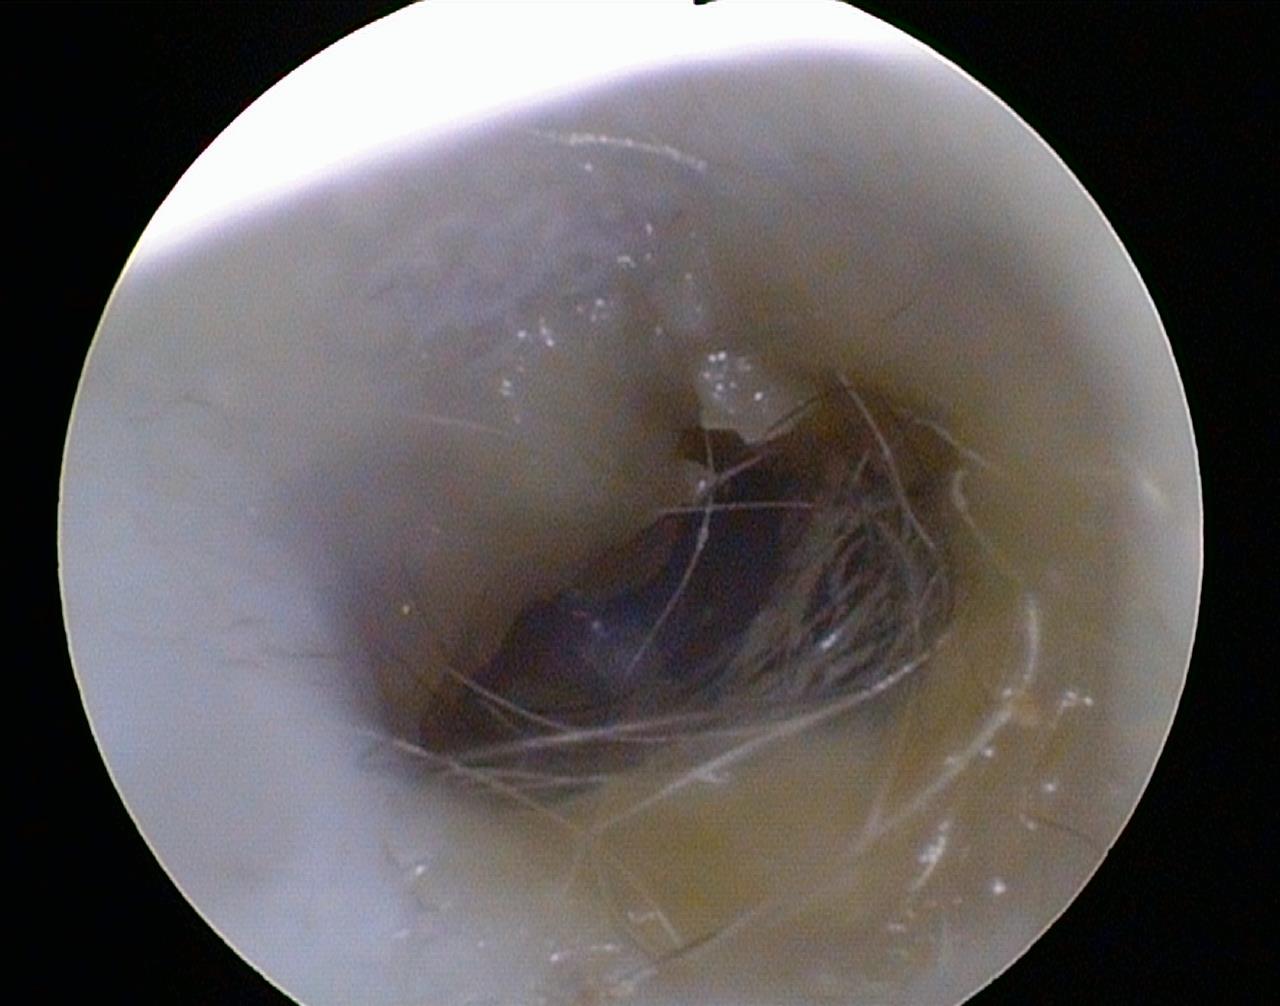

Zunehmendes Kopfschütteln, u. U. gepaart mit beginnendem Kratzen des seitlichen Kopfbereiches sind erste Anzeichen einer Entzündung im Bereich der Ohren. Die Untersuchung mittels Otoskop ermöglicht das „direkte Hineinschauen“ in den äußeren Gehörgang. Dies ermöglicht in den meisten Fällen schon eine Diagnose mit nachfolgender Therapie.

Ist eine darüber hinaus reichende Untersuchung des äußeren Gehörganges notwendig, umfasst diese die Probenentnahme zur weiteren Diagnostik. Dies ist in vielen Fällen für den Patienten schonend endoskopisch möglich.